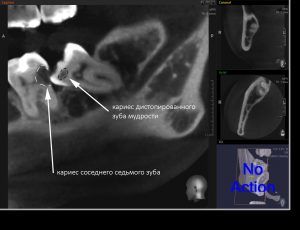

С дистопированными зубами мудрости всё, вроде как, тоже понятно — ввиду их расположения, затрудняется гигиена полости рта, и эти зубы довольно быстро поражаются кариесом. Бывает хуже, если кариес распространяется на соседние семерки, которые, в отличие от восьмёрок, в функциональном отношении весьма важны. Нередко кариес появляется на самой дальней и плохо обозримой поверхности зуба. И человек замечает его лишь тогда, когда всё это дело начинает болеть. То есть, слишком поздно.

- Аномально расположенный (дистопированный) зуб мудрости. Ему не хватило места и он либо наклонился в какую-то сторону, либо остался наполовину в десне. Функционировать такой зуб никогда не будет, но он создаёт проблемы как для прикуса, так и для соседних зубов. Нужно ли его удалять? Безусловно.